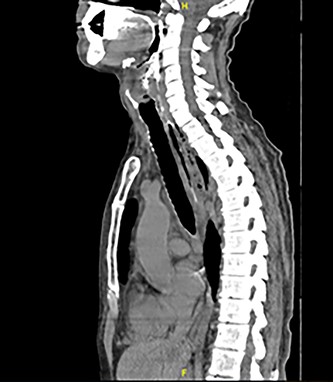

Intravenous Meropenem, Metronidazole and Fluconazole were continued, and he remained nil by mouth with nasogastric tube feeding. Water-soluble contrast swallow was undertaken after repeat CT showed emphysema progression (Fig. 3). A left sided oropharyngeal perforation was suggested.

Axial planes CT neck and thorax showing left parapharyngeal abscess with tracking into the prevertebral space, significant progression of air pockets in mediastinal and cervical soft tissue extending to right axillary region.